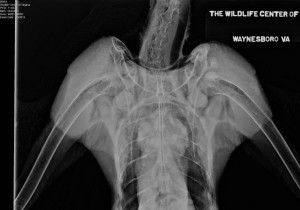

TODAY'S UPDATE FROM WCV ON NX January 3 update NX was anesthetized on the morning of January 3 for another set of radiographs. Dr. Miranda reports that the avulsed piece of bone in NX’s injured shoulder is healing and appears to be reattaching. While NX’s left shoulder still appears to be “dropped” a little on the radiograph, Dr. Miranda is pleased with NX’s range of motion and how that shoulder feels. The boney changes in the humeral head appear to be unchanged from prior radiographs. The veterinary team will continue to monitor on future x-rays. NX’s eye injury is also resolved – Dr. Miranda says that the vitreal fracture in NX’s right eye has healed. After recovering from anesthesia, NX was moved to one of the Center’s “C-pens” – a small outdoor enclosure for raptors that are not quite ready to be moved into a flight pen. Enclosures in this complex measure about 8’ x 16’ and are large enough for birds to hop and flap to different perches, but are not large enough for flight. At this point, the Center vet and rehabilitation staff do not want NX to over-extend her healing shoulder and wing by flying. NX is scheduled for another set of radiographs on Monday, January 16. Pending satisfactory radiographs, she will then be moved into a flight pen.